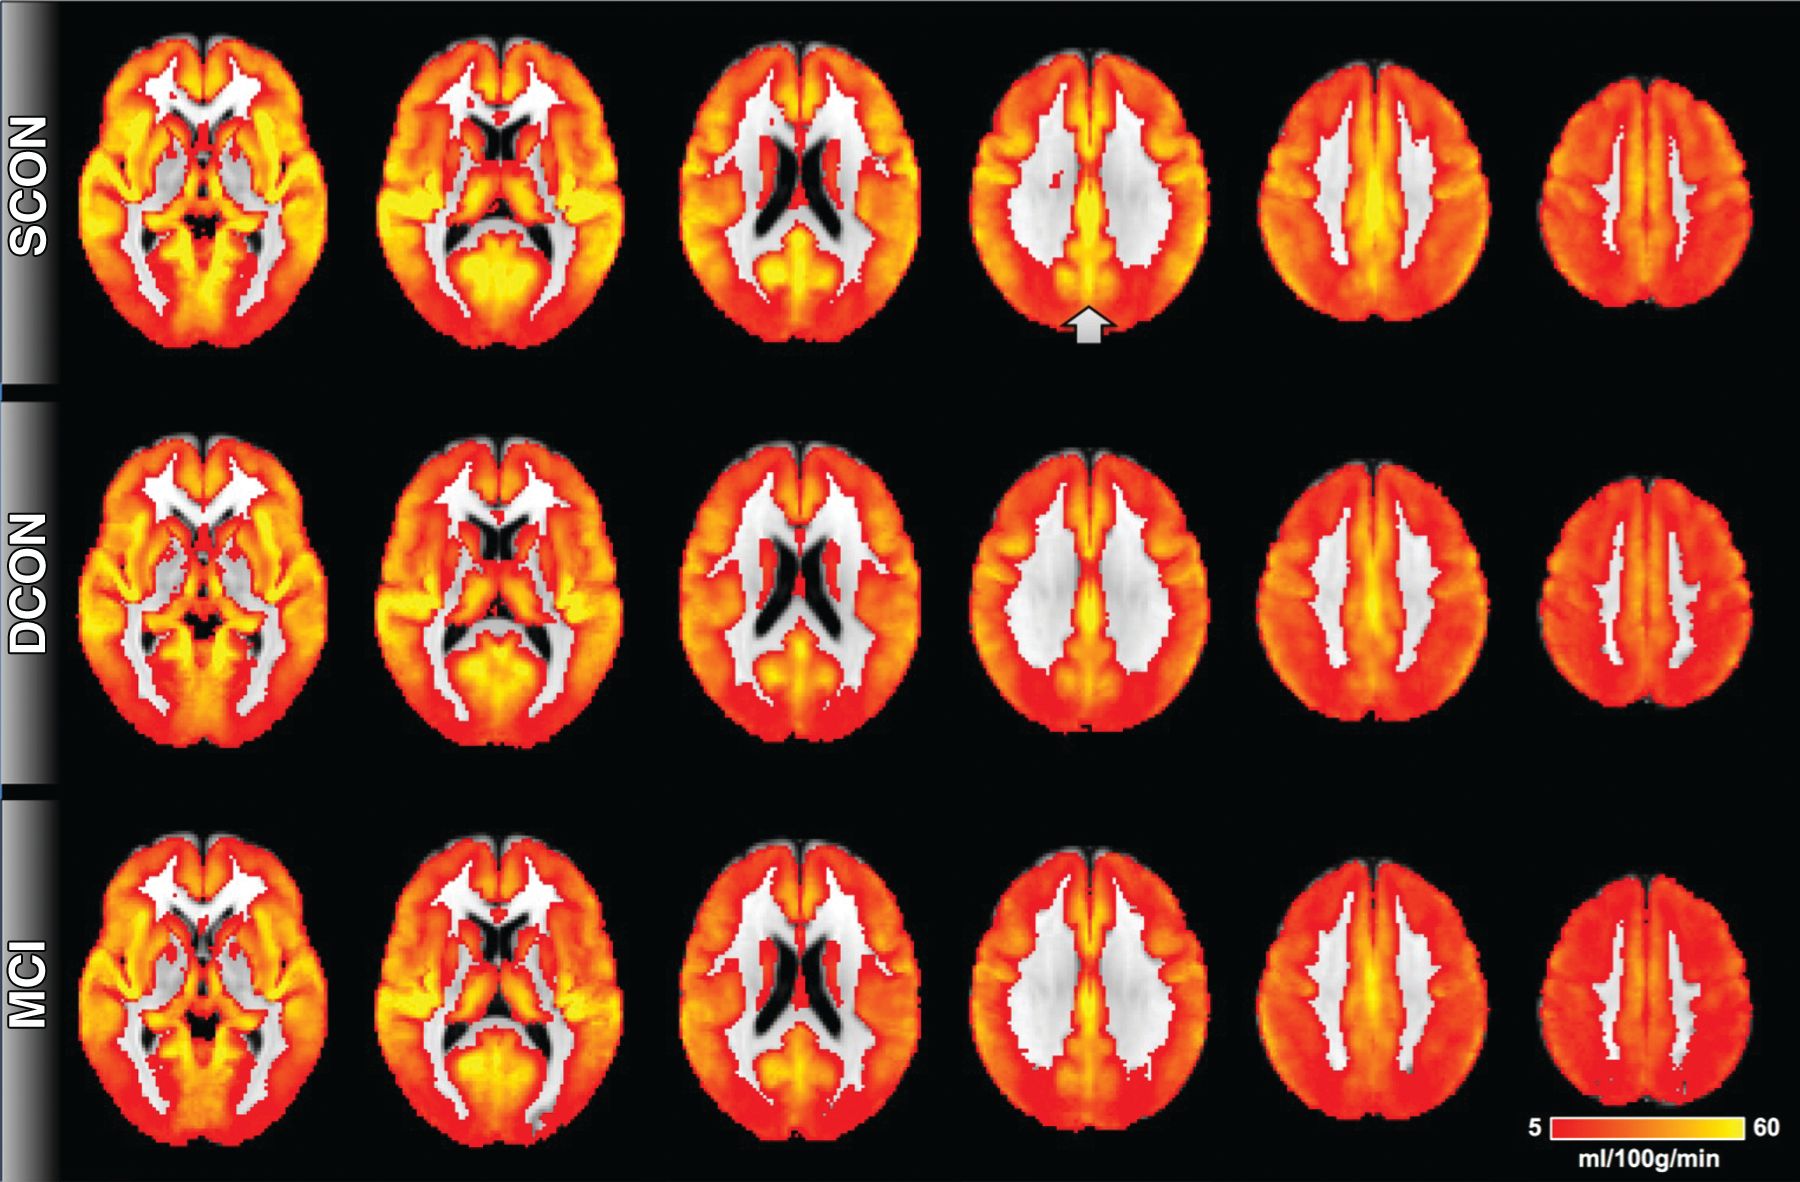

Arterial spin labeling has shown changes in the posterior cingulate cortex among patients who went on to experience cognitive decline.